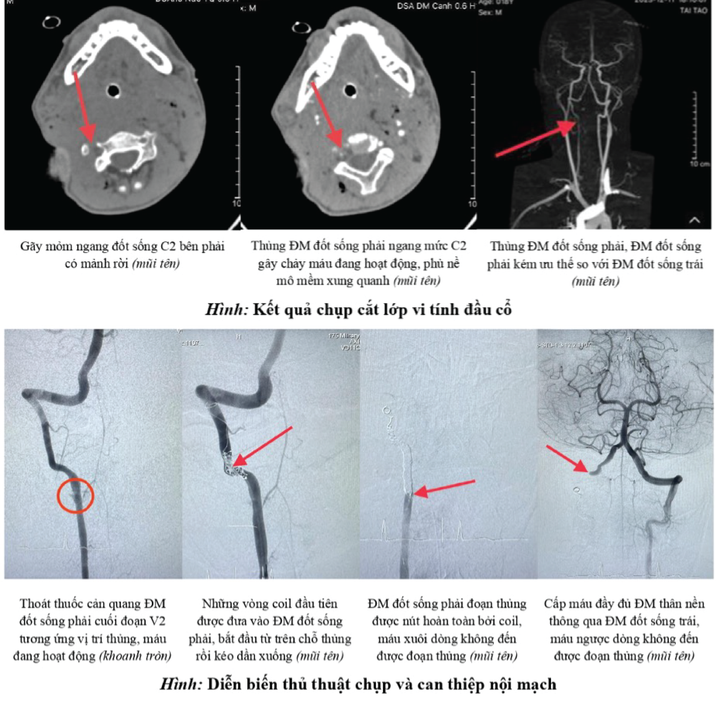

Ảnh chụp cắt lớp vi tính đầu cổ khu vực bị tổn thương và quá trình can thiệp nội mạch. (Ảnh: BVCC)

Tiến sỹ, bác sỹ Tạ Vương Khoa, trưởng ê-kíp can thiệp, cho biết bệnh nhân bị thủng động mạch đốt sống, có nguy cơ đe doạ tính mạng do nguồn cung cấp máu lên thân não bị gián đoạn.

Theo BS Khoa, việc điều trị thủng động mạch đốt sống do vết thương xuyên thấu rất khó khăn. Có hai phương pháp xử lý là phẫu thuật và can thiệp nội mạch.

Phẫu thuật xử lý một động mạch đốt sống đang chảy máu được xem là một trong những loại phẫu thuật phức tạp và nhiều thử thách nhất, kể cả đối với những phẫu thuật viên giàu kinh nghiệm, đặc biệt khi vị trí thủng ở cao như trường hợp này.

Còn can thiệp nội mạch qua da là luồn dụng cụ trong lòng mạch máu đến vị trí động mạch đốt sống bị thủng, xử lý chỗ thủng bằng các vật liệu phù hợp. Đây là kỹ thuật "sinh sau đẻ muộn" nhưng đã nhanh chóng chứng minh ưu điểm so với phẫu thuật.

Vì vậy ê-kíp quyết định sử dụng phương pháp can thiệp nội mạch và đã xử lý thành công động mạch đốt sống bị thủng. Sau đó, bệnh nhân tiếp tục được các bác sĩ nhiều chuyên khoa theo dõi, thám sát kỹ lưỡng, xử lý hiệu quả các sang thương kết hợp.